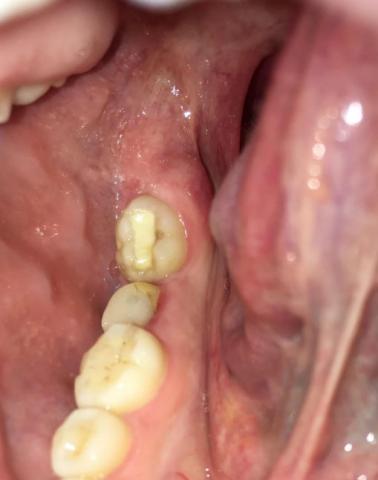

This intra-oral image shows a partially erupted posterior molar with surrounding inflamed gum tissue. The tooth is covered by soft tissue, creating a pocket that traps bacteria and debris. This presentation is consistent with a localized gum infection associated with a partially erupted or impacted tooth.

-

Partially erupted molar

Gum tissue covering part of the tooth crown

Redness and swelling of surrounding soft tissue

Visible plaque and debris accumulation

Adjacent teeth appear intact

Localized pericoronal infection (pericoronitis)

Inflammation related to partially erupted molar

Early-stage soft tissue infection with risk of progression